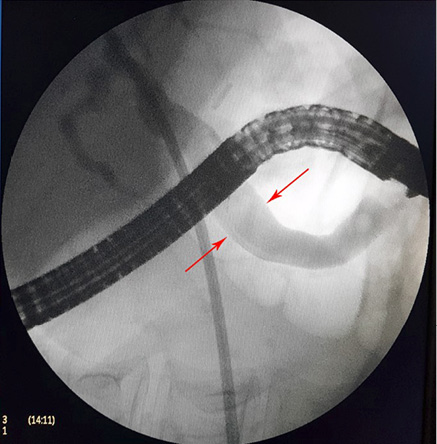

3 pav. Askaridės šalinimas iš BTL, atliekant duodenoskopiją

Pacientei įtarta pilvo skausmų priežastis – tulžies latakų akmenligė, nesant mechaninės geltos. Priimtas sprendimas atlikti duodenoskopiją ir ERC tyrimą. Duodenoskopijos metu įvertinta, kad papilla Vateri yra po PST procedūros. Kontrastavus BTL, pastebėtas >5 cm ilgio 4 mm skersmens prisipildymo defektas lygiais kontūrais. Naudojant Dormia krepšelį, iš tulžies latako pašalintas prisipildymo defektas – askaridė (3–5 pav.). Atlikus procedūrą, pacientės sveikatos būklė pagerėjo, pilvo skausmas regresavo, nesikartojo. Papildomai atlikta dehelmintizacija mebendazolu, antihelmintiniu vaistiniu preparatu („Vermox“).